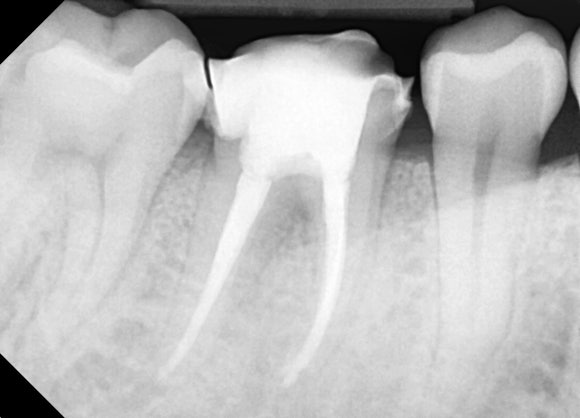

20250329

수차례 치아 내부를 청소하고 소독하기를

반복했습니다.

두 달 정도 걸려 신경치료를 마무리했습니다.

(좌) 재신경치료 전 (우) 재신경치료 후 (20240329)

뿌리 끝에 매달려 있던

검은 그림자의 내부로

몽글몽글 새 뼈가 재생되는 것을

관찰할 수 있습니다.